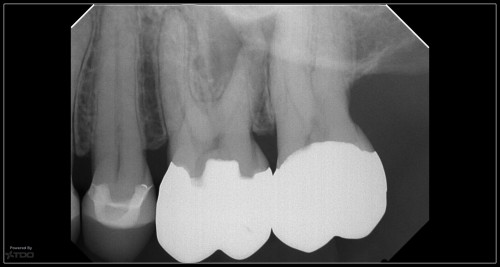

Had many emails on how to interpret some of the sections from our “fracture case” […]

How to detect a biofilm

By Gary Carr / February 27, 2019